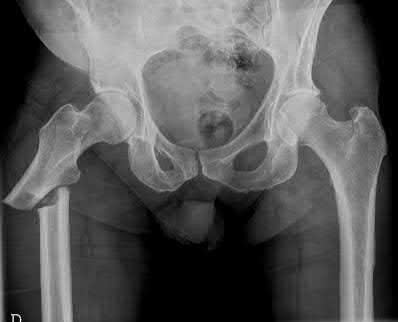

A 35-year-old man presents to the ED as the restrained driver of a high speed motor vehicle collision complaining of hip, chest, and abdominal pain. He becomes diaphoretic, tachycardic, and hypotensive in the trauma bay and is noted to have diminished lower extremity pulses. He is found on ATLS workup to have mediastinal widening.

Which of the following injuries is most associated with thoracic aortic injury?

Thoracic aortic rupture is associated with posterior hip dislocation in deceleration trauma mechanism of injuries.

Posterior hip dislocations are infrequently associated with local vascular injuries. With bilateral perfusion deficits, more proximal large vessel trauma should be considered, and in this situation, thoracic surgery should be involved emergently. Screening chest x-ray in the trauma bay should be reviewed for widened mediastinum, suggestive of aortic injury, as shown in illustration A. Given the high energy mechanism associated with these injuries, a full ATLS trauma survey must be done for every patient.

Marymont et al. studies the association between posterior hip dislocation and thoracic aortic injury. They performed a retrospective chart review of 89 posterior hip dislocations and found 8% had an aortic injury. Although not statistically significant, they note the importance of evaluation for aortic injury in patients with posterior hip dislocations given its emergent life-threatening nature.

In addition to associated chest injuries, Schmidt et al. highlight the importance of evaluating the ipsilateral knee after high-energy traumatic hip dislocation. In a prospective study, they identified a 93% rate of ipsilateral knee injury on MRI including effusion (37%), bone bruising (33%), and meniscal tear (30%) as the most common. They recommend a thorough exam but also expanded use of knee MRI after hip dislocation.

Illustration A shows an example of chest x-ray with a widened mediastinum, suggestive of thoracic aortic injury.

Answer choices A,B,D,E show other injury patterns: Answer A - Right femoral neck fracture

Answer B - Right intertrochanteric hip fracture Answer D - Right subtrochanteric hip fracture

Answer E - Right superior and inferior pubic rami fractures